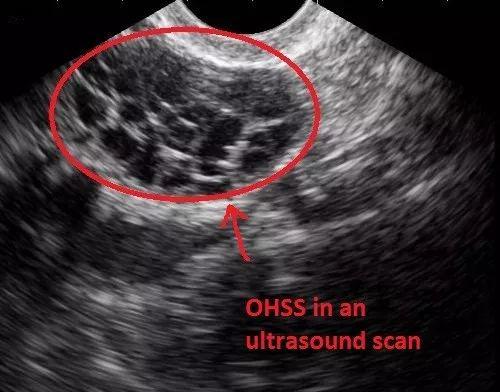

而情况严重者,还可能引起卵巢过度刺激综合征(Ovarian Hyper-Stimulation Syndrome, OHSS)。

自然周期下的卵巢;促排卵后的卵巢;卵巢过度刺激下的囊性增大

这是一种人体对促排卵药物产生的过度反应而引起的医源性疾病。

其主要临床表现为卵巢囊性增大、毛细血管通透性增加、体液积聚于组织间隙,引起腹腔积液、胸腔积液,伴局部或全身水肿。

卵巢过度刺激综合征的发生率 ,大约在5%之间,说高不高说低也不低。供卵者轻则腹痛呕吐,重则腹水、血栓、肾衰竭、中风乃至死亡。

超声下显示的卵巢过度刺激综合征